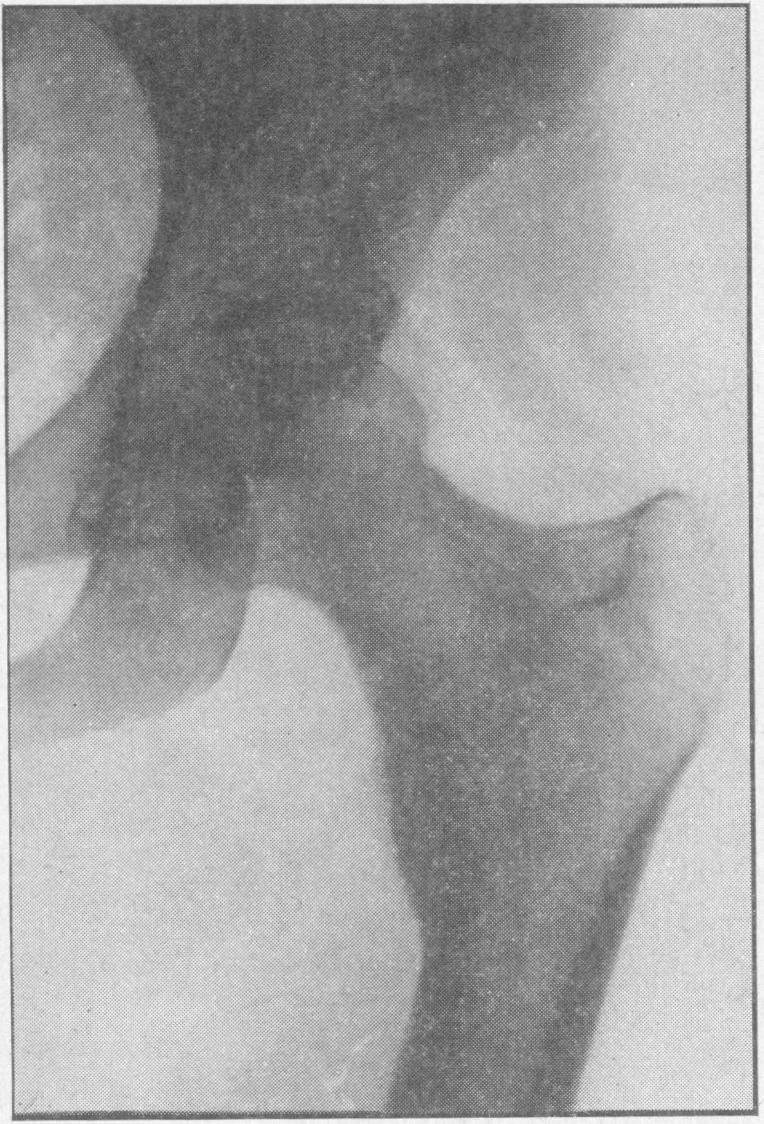

TUCKER W E

Proc R Soc Med. 1955 Aug;48(8):613-4. doi: 10.1177/003591575504800810.